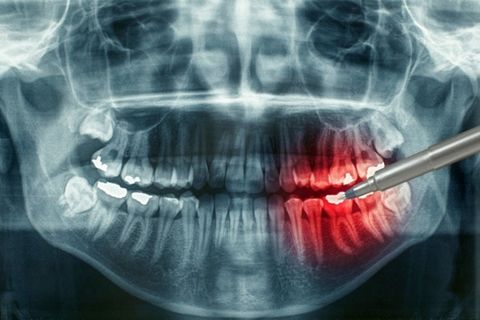

При диагностике остеомиелита челюсти врач осуществляет тщательный осмотр пациента, проводит рентгенодиагностику. Дополнительно необходимо сдать общий и биохимический анализ крови. А для установки возбудителя и проверки его чувствительности к антибиотикам надо сделать бактериологическое исследование гноя из свищей.

В процессе диагностики остеомиелита челюсти врачу важно отделить этот диагноз от других, которые имеют схожие симптомы — например, острого пульпита, острого периодонтита, гайморита, абсцесса мягких тканей и т. д. Точная постановка диагноза значительно увеличивает шансы пациента на полное и более быстрое восстановление.